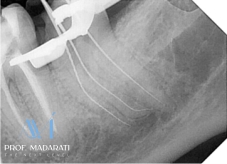

Access and Initial Negotiation:

Following access cavity preparation, the two mesial canals were initially scouted using a C-file #8 repeatedly, followed by a K-file #10 to establish patency to the full working length.

Glide Path Preparation:

Given the severe curvature, a dedicated glide path was prepared using rotary path files with a minimal taper (2-3%). Specifically, PA rotary files (Denco Medical) in sizes 13/.02, 16/.02, and 19/.02 were used sequentially to create a safe, smooth pathway.